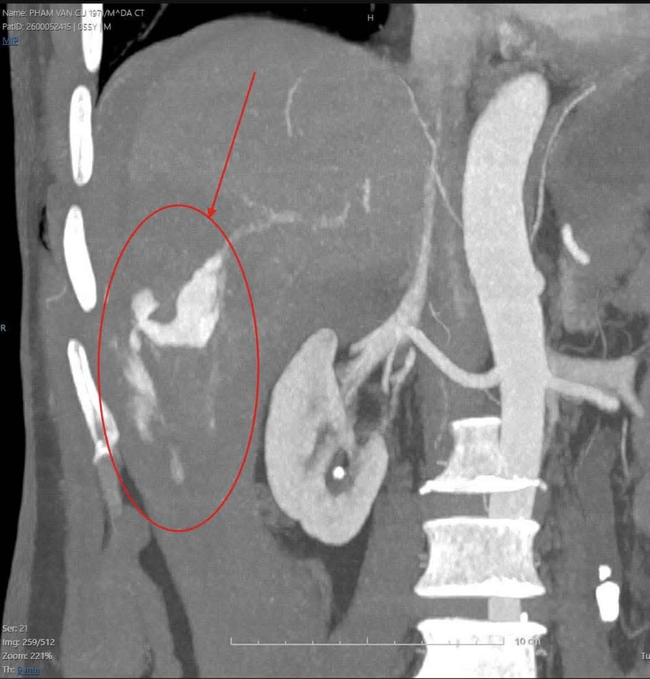

Kết quả chụp cắt lớp vi tính mạch máu bơm thuốc cản quang (CTA) cho thấy bệnh nhân bị chấn thương cực kỳ nghiêm trọng: Vỡ gan độ IV tại hạ phân thùy VI, máu chảy ồ ạt trong ổ bụng. Ngoài ra, bệnh nhân còn bị gãy hàng loạt xương sườn số 6, 7, 8, 9 và 10 bên phải.

Vùng gan vỡ chảy máu nguy kịch.